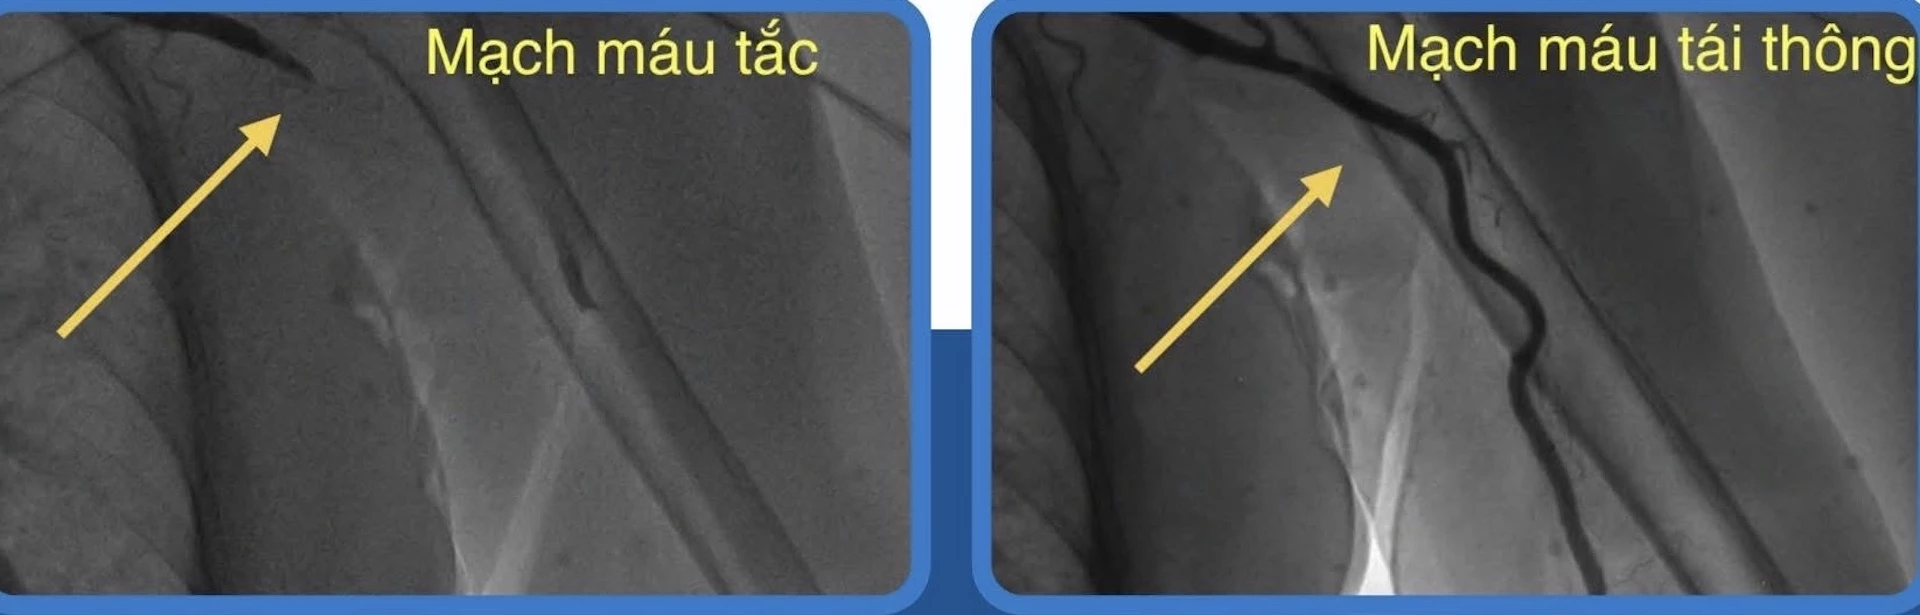

Trước tình trạng nguy kịch của bệnh nhân, ê-kíp bác sĩ Khoa Tim mạch can thiệp của bệnh viện đã nhanh chóng tiến hành chụp mạch và nong bóng khai thông động mạch cánh tay trái dưới hệ thống chụp mạch số hóa xóa nền. Sau can thiệp, dòng chảy của máu được khôi phục hoàn toàn đến vùng cẳng và bàn tay trái. Nhờ đó, các triệu chứng lâm sàng của bệnh nhân được cải thiện hoàn toàn, mạch tay rõ, bàn tay hồng hào, tay ấm trở lại.

Hình ảnh trước và sau dòng máu được tái thông.